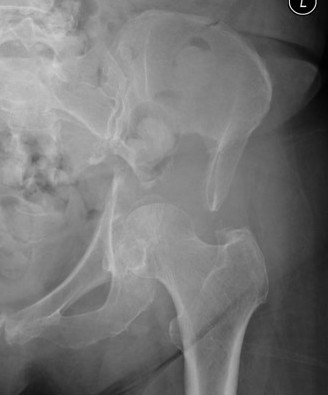

Acetabular Metastasis

Harrington classification

| Type I |

Minor cavitary defect Medial and superior walls intact |